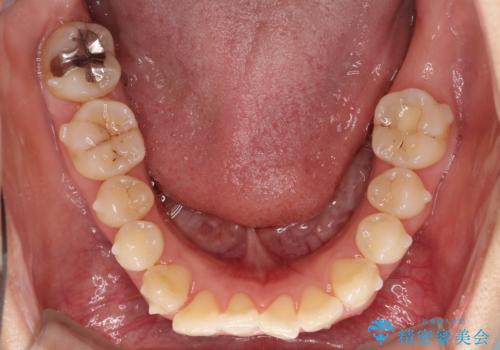

【インビザライン】前歯の凸凹をなおしたい

- 前歯の凸凹をなおしたいことを主訴にインビザラインにて矯正治療を行いました。

患者様にしっかりとインビザラインを使用して頂けたことで綺麗な仕上がりとなりました。